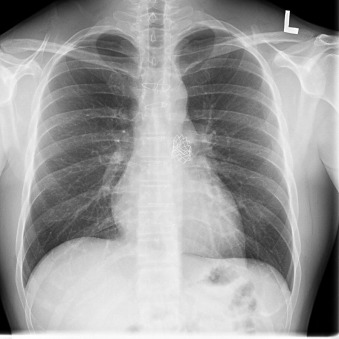

Percutaneously inserted heart valves are evident on chest radiography.

The position of percutaneous heart valves can be visualized by chest radiography, as can some complications and dysfunction.

Transcatheter/percutaneously inserted heart valves are increasingly implanted. Most commonly, they are inserted into the pulmonic position or right heart conduits in the previously repaired congenital heart disease population ( Figs. 13-1 and 13-2 ) and into the aortic position ( Table 13-1 ; Graphics 13-1 and 13-2 ; Figs. 13-3 to 13-10 ), but they can also be placed into atrioventricular valve positions and into bioprostheses or conduits in any position.

Percutaneous valves are generally supported by radiographically obvious stents, the design of which allows for initial contraction of the prosthesis onto a catheter and release/self-expansion from the catheter.

Percutaneous/transcatheter heart valves are constructed of either bovine jugular venous valves that are suspended on wire mesh cages (Bonhoeffer design/Melody Transcatheter Pulmonary Valve–TPV, Medtronic), or consist of a valve created from bovine pericardial tissue that is suspended on wire mesh cages (Edwards Sapien and Medtronic CoreValve). Percutaneous aortic valve implantation is currently one of the most rapidly proliferating percutaneous interventions in the world ( Figs. 13-11 to 13-13 ).